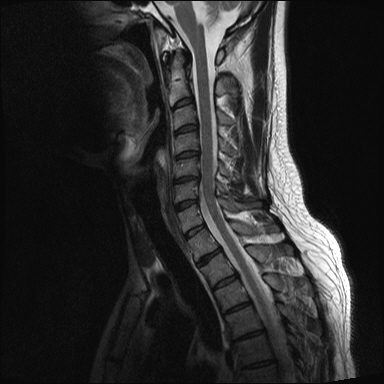

ȸ ϸ鼭 ۼ Դϴ. Ű 172 72 35 ˰Ե ͳ õ ijħ ǥغ ϱ ȣϽ 1C.ڵӸ 1C.ٸǷ 1C.ټ Ǹ 1C.ٱ () 1C.߷ () 1C.Ƿ () 2C.ھȱ, 2C.ڴ 2C.ھ˷⼺(˷) ḷ 2C.ٴ, 2C.ٰḷ 2C., 2C.ٺ, 2C.ٸ 2C.پ˷⼺(˷) 3C.ġ Ű 3C. 4C. 6C.ڸ 6C.ھ Ḳ 6C.ڻ 1T.ȣ 4T. 3T.ȯ, 5T.ȯ ҷ, 6T.ټ 6T.ٽƮ 9T.˷ 10T.ٸǷ 2L. 㰡 2L.ȣ 3L. 3L.ڹ 4L.° 4L.ھƷ 4L.ڿ, 4L.ڵ Ʒ 5L.ڴٸ Ʒκ̳ 5L.ڹ߸̳ õ().¦ٸ ()ũ( ߰Ż) Ը Ͽ ũ(߰Ż), ũ(߰Ż)ġ, , Ḳ , , Ḳ ġ ȱ ǰϰų ڸ, , ڰ , , Ǵ ġ ô ¦ٸ(ٸ̰ ٸ) , 㸮 ̳ ġ Ƹ ġ ħ ߷, , нɷ 帶, ɱٰ, ɺ ڸǥغ ǥغ ϰ ߴ ġ 1. ũ 1) ߺñ: 1 Ӹ ־ ʹ 2)˻ : ** x-ray MRI Ȯ 3,4,5 ũ ̸, Ư 4 ũ ¦ Ƣ . 3)ġ: Ű漺 , ġḦ ʾҰ, Ư ǿ ħ °, Ȱġ(Ȳ,ħ, ȸ ) . 4)ġ : 1.Ͻ ȿ ־, ð 2. 㸮() 1) ߺñ: 3 ϱ ٳѱ⸦ ڱ 㸮 , ģ ƮĪ شٸ 㸮 ȭ ƮĪ Ʋ . 2)˻ : ǿ 㸮 ġ . 3)ġ: ħ ȰġḦ 4)ġ :Ͻ ȿ ־ ɰų 㸮 3. ڰ 1) ߺñ: ڰ̰ ִ Ȯ 5 Ǵܵ 2)˻ : 6~7ð 2~3ð ڸ , ȣ 3)ġ: ġḦ ް , ڰ *** ߿ Ƽ ϰ 4)ġ : ڸ 4. 1) ߺñ: 2~3 ְų Ͻ ־ 2)˻ : ˻縦 ʾ, ʰ ô ó 3)ġ: 4)ġ : 5. ô 1) ߺñ: 3 ڿ ɾƼ ٸ µ ٸ ª 2)˻ : 7 Ȱ X-RAY ణ ô ִٰ Ǹ 3)ġ: ġ 4)ġ : Ͻ 6. (˷ ḷ) ȱ 1) ߺ: 5 2)˻ : Ű 3)ġ:1~2 ѹ ް Ⱦ ֱ ְ 4)ġ : , ħħϰų 7. , Ѽ ȣ ߺñ: ɸ Բ ڰⰡ , ڸ, ä, 2)˻ : Ḧ ʾ, ڰ Ⱑ ư, Ѽ Ҵ Ȳ µ ϰ ȸ ȭ ˷ֽ ǥغ ϴ ڸ ϴ. 㿡 ħ ȸԲ ˷ֽ Ư ġü ġὺƮĪ Բ ġ ȭ ʰ ȸǴ ڼ ϴ ϴ. ˷ֽ ͵ ̳ ǰ ͳݿ ִ ٸ Դϴ. ϴ ȭ Ÿϴ. ϴ. پٰ ϴ. ϴ پų ϴ. 30и 30 ̻ ϶ ϼ̽ϴ. 30иٴ ϰ ҷ ߽ϴ. Ȳ ٷ ϴٰ ٽ ϴ. ķ 鵵 Ÿϴ. γ ȸԲ ڵȽϴ. ٽ ȭּż Ȳ ϰ ʰ ּ̰ ڼ ణ ߸ϰ ־ ֽð ʰ ˷ּ̽ϴ. ȭ Ŀ ߰ ȭ ߾ ߴµ ϴٰ 1 ȭ ѹ ʾҾϴ. ˷ֽ ˷ֽ 뿡 ణ ̴ ε ̼ϰ ٸ ̷ Դϴ. ʰ ϴ ڼ ü ٽ ϰ ˷ּ̰ а ߴص ϰ ˷ֽ θ ϶ ϼ̽ϴ. ˷ֽŵ Ȱ ϰ غ ı øڽϴ. ȸ 㵵 ű Դϴ. ۼ ıԴϴ. http://najari.kr/Board/index.php?Code=free1&No=5141&action=View&st=&sn=&sc=&Keyword=&Page=1 |